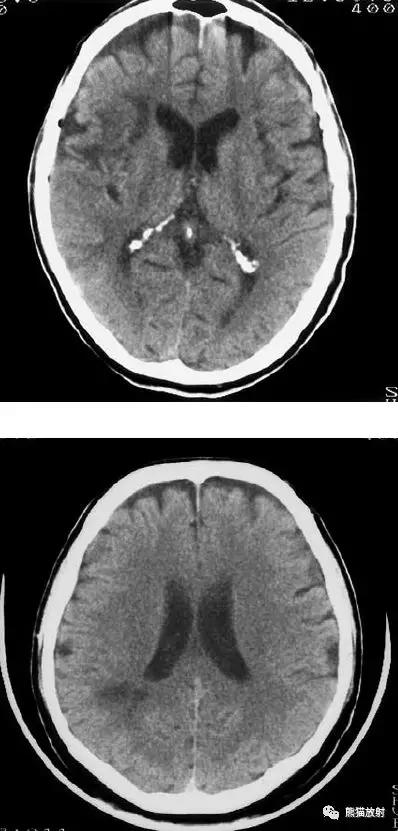

大脑中动脉区梗死:部分梗死,仅累及左侧浅表区域。

左侧大脑中动脉区完全梗死,对邻近的侧脑室产生占位效应;右侧可见其他较小的缺血性低密度区。

左侧尾状核头脑梗死;右侧外囊腔隙性脑梗死。